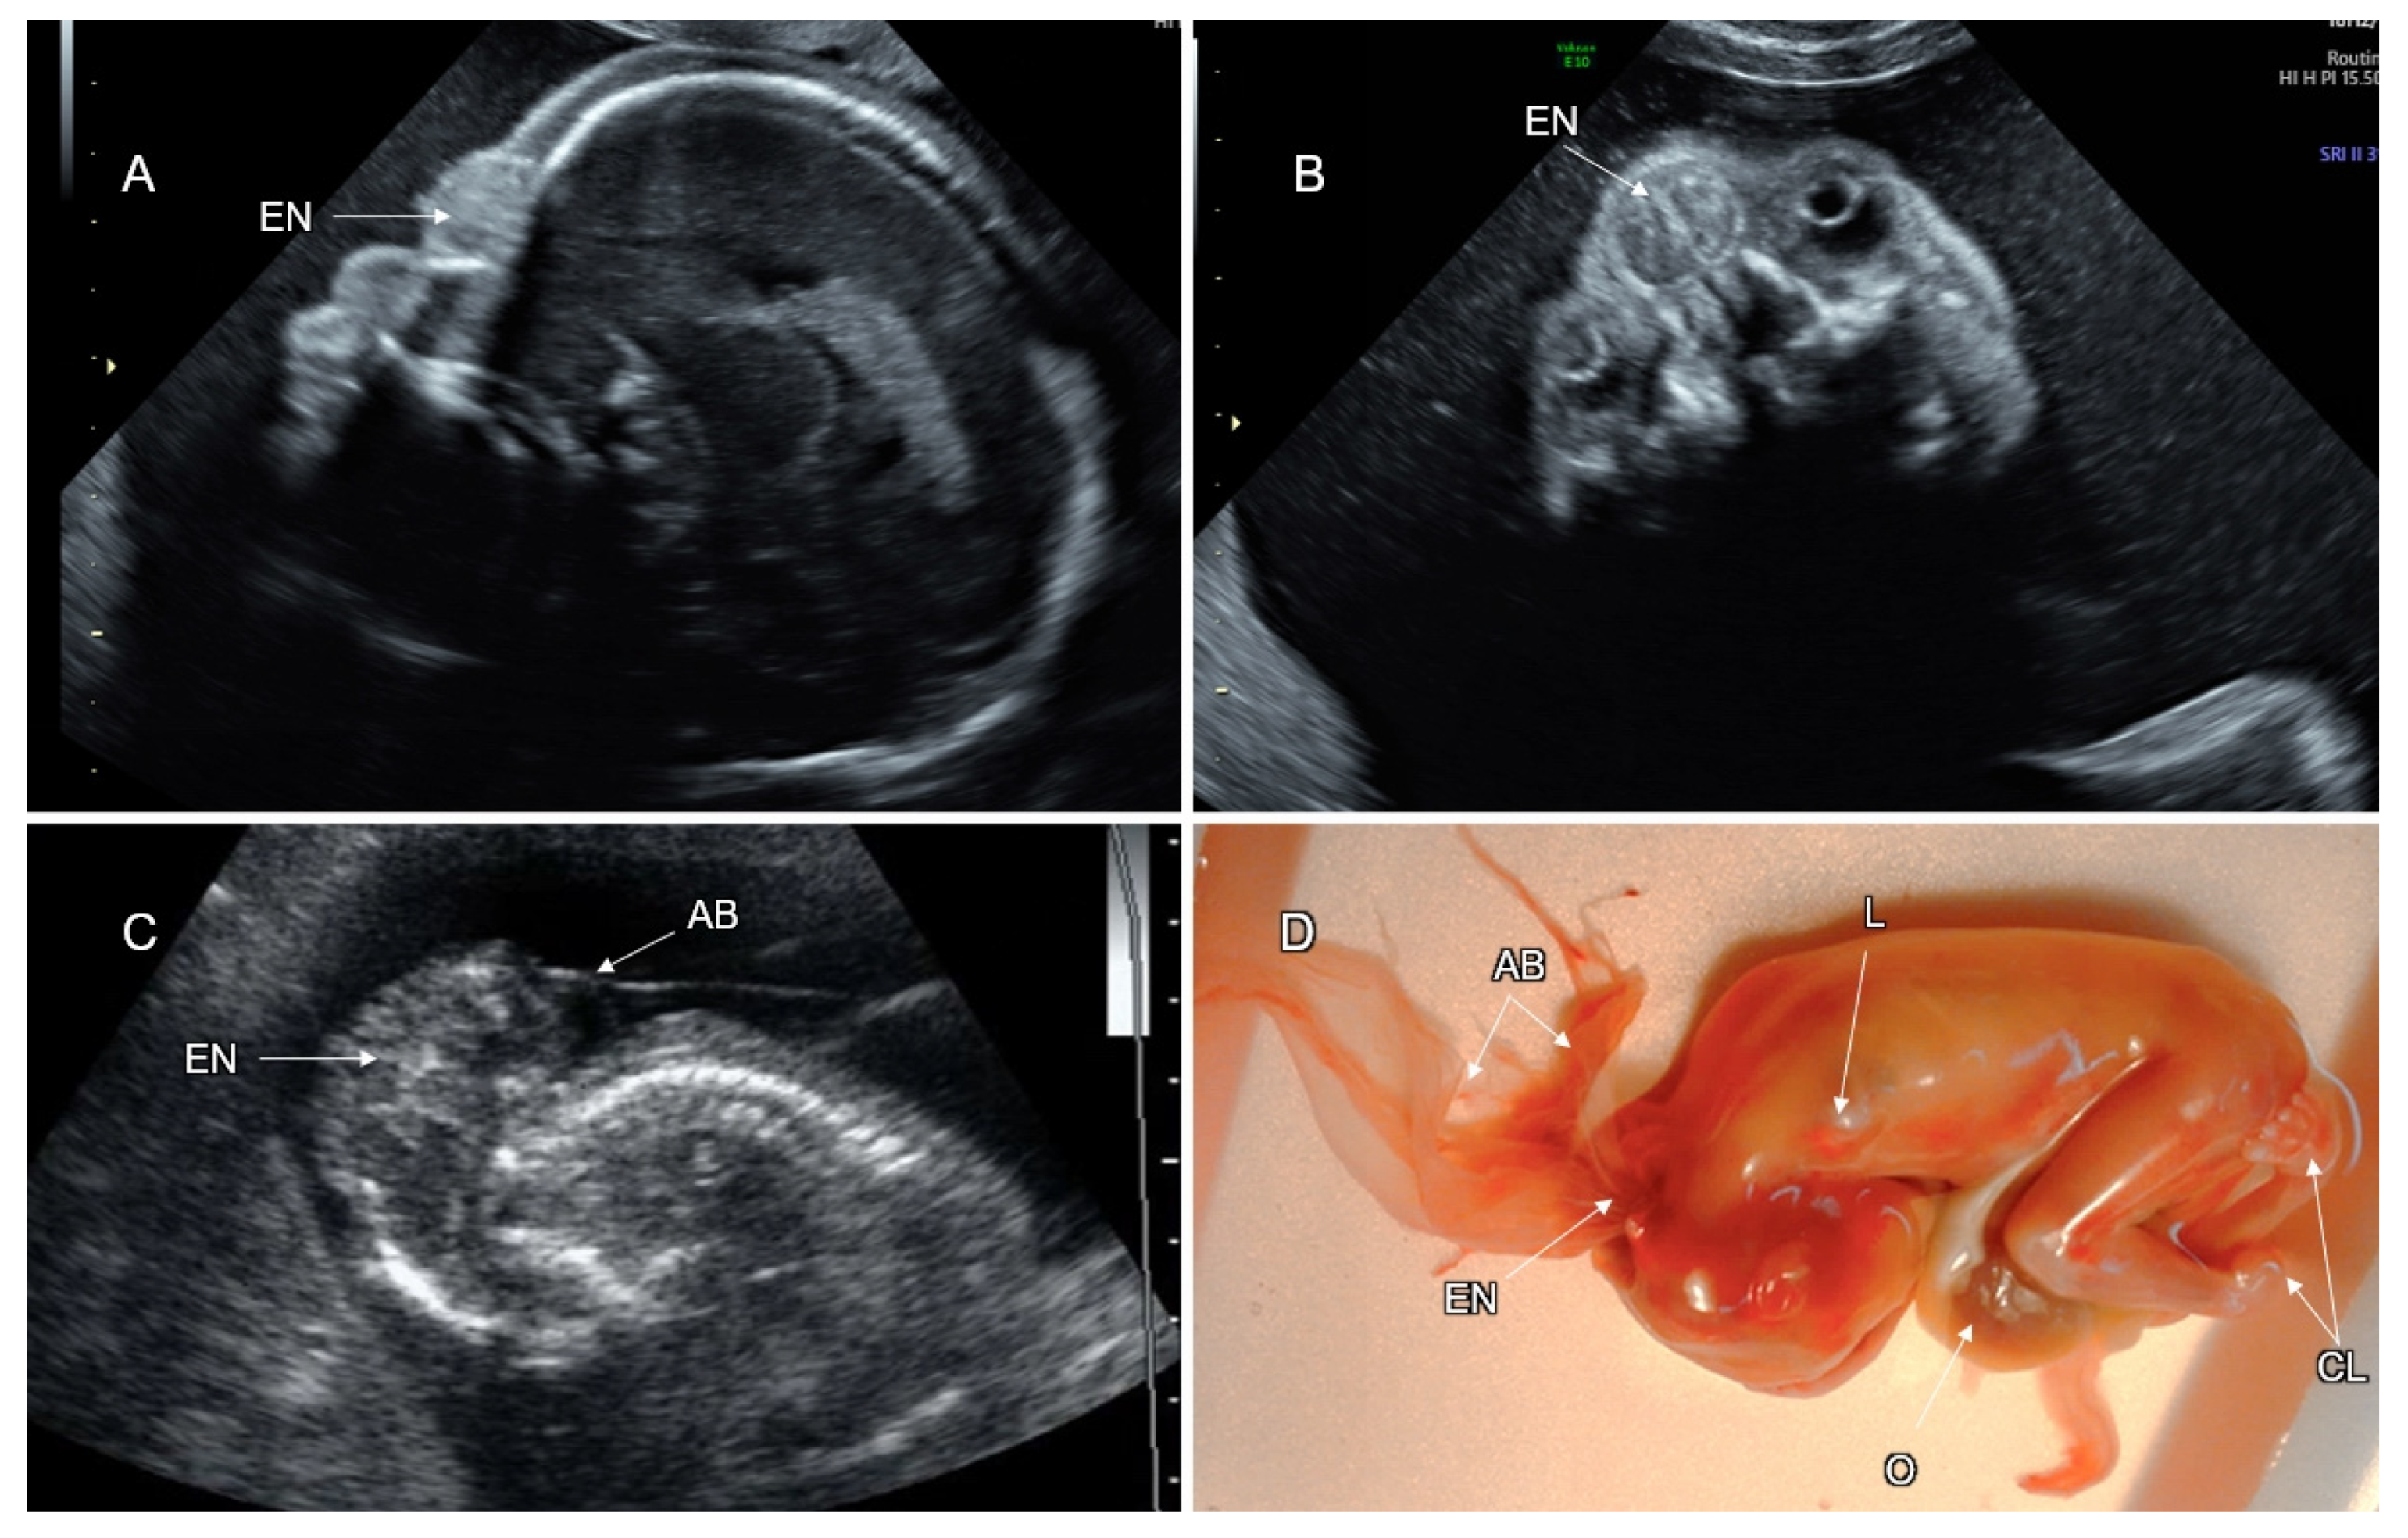

3.1. Cranial NTD

3.2. Spinal Dysraphism